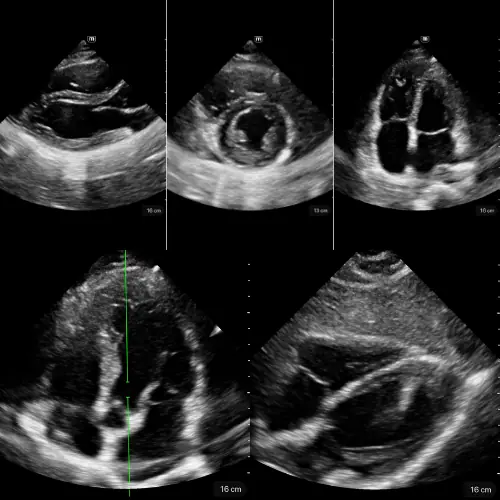

Fonction Systolique du VG

L’œil clinique comme capteur hémodynamique